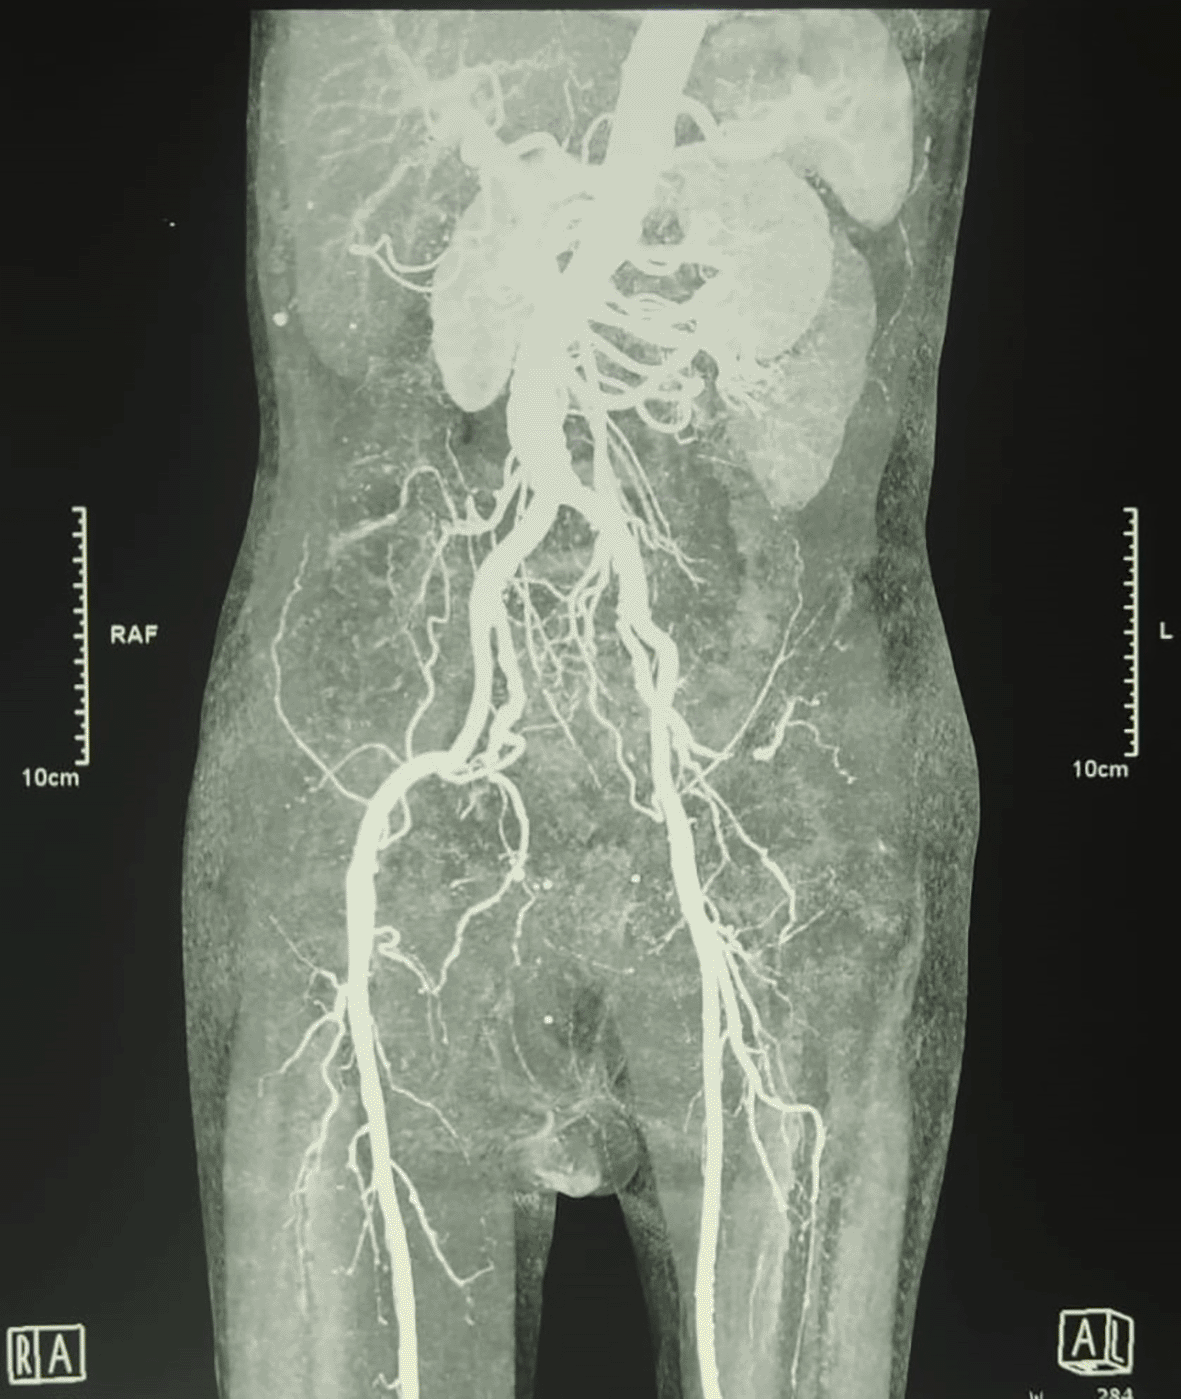

An urgent radiologic investigation with Doppler ultrasound of the penile and pelvic computerized tomography (CT) angiography revealed no occlusion nor thrombus on the arteria that supplies the penile (Figure B).

Penile necrosis is linked to thrombotic events and calcium deposits in dialysis patients.13 Another study also reported penile necrosis secondary to purpura fulminans.15 One study in Japan described fifteen patients with penile necrosis due to calciphylaxis and a long history of diabetes.16 In this condition, it is clearly understood that diabetic vasculopathy and calcium deposits can become a thrombus which causes impaired blood flow to penis. In our patient, he had no comorbid precipitating thrombus vasculopathy. Although the patient is an active smoker, we still cannot conclude that this is the cause of penile necrosis. Uniquely, the CT angiography investigation of our patient did not reveal any occlusion or thrombus.